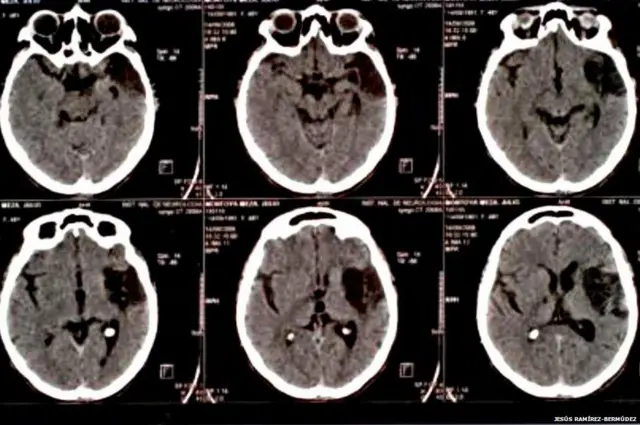

Los indicios neurológicos incluyen un índice metabólico muy bajo en regiones del cerebro responsables de la introspección, el achicamiento o aumento del cerebro y el daño a la parte del cerebro que está detrás de la frente, que controla los pensamientos, el razonamiento y el comportamiento.